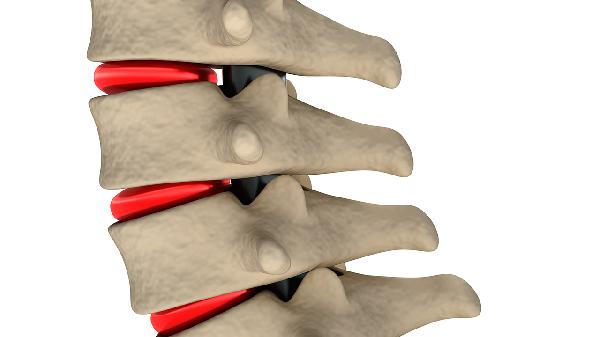

5、疗效评估

常规用药3个月后应通过X线或CT评估骨赘变化情况,若出现关节活动度持续恶化需考虑调整治疗方案。疼痛症状缓解后不可擅自增量,过度用药可能导致骨代谢紊乱。突发关节肿胀或持续性麻木需警惕药物相关性关节滑膜炎。